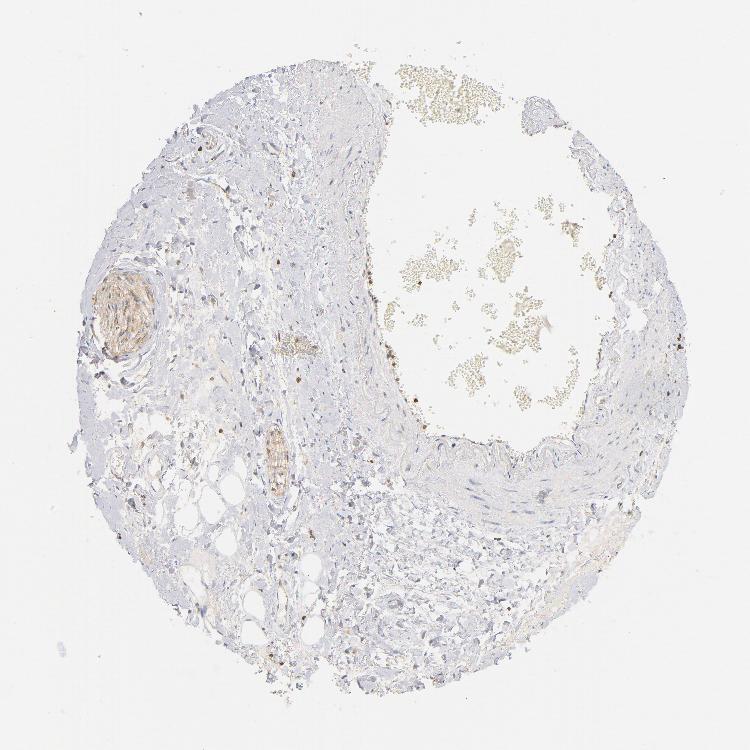

SOFT TISSUE 2 - Antibody stainingi

Antibody staining in the annotated cell types in the current human tissue is reported as not detected, low, medium, or high, based on conventional immunohistochemistry profiling in selected tissues. This score is based on the combination of the staining intensity and fraction of stained cells.

Each image is clickable and will lead to virtual microscopy that enables deeper exploration of all samples and also displays staining intensity scores, fraction scores and subcellular localization as well as patient and tissue information for each sample.

Antibody HPA021616Antibody CAB004035Antibody CAB047324Antibody CAB075739

Chondrocytes --Not detected-

Fibroblasts Not detectedNot detectedNot detectedNot detected

Peripheral nerve Not detectedLow-Low